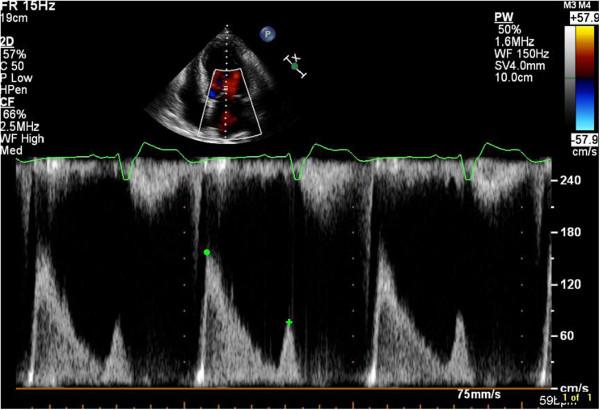

Echocardiographic assessment of ischemic mitral regurgitation.

Ischemic mitral regurgitation is an important consequence of LV remodeling after myocardial infarction. Echocardiographic diagnosis and assessment of ischemic mitral regurgitation are critical to gauge its adverse effects on prognosis and to attempt to tailor rational treatment strategy. There is no single approach to the echocardiographic assessment of ischemic mitral regurgitation: standard echocardiographic measures of mitral regurgitation severity and of LV dysfunction are complemented by assessments of displacement of the papillary muscles and quantitative indices of mitral valve deformation. Development of novel approaches to understand mitral valve geometry by echocardiography may improve understanding of the mechanism, clinical trajectory, and reparability of ischemic mitral regurgitation.